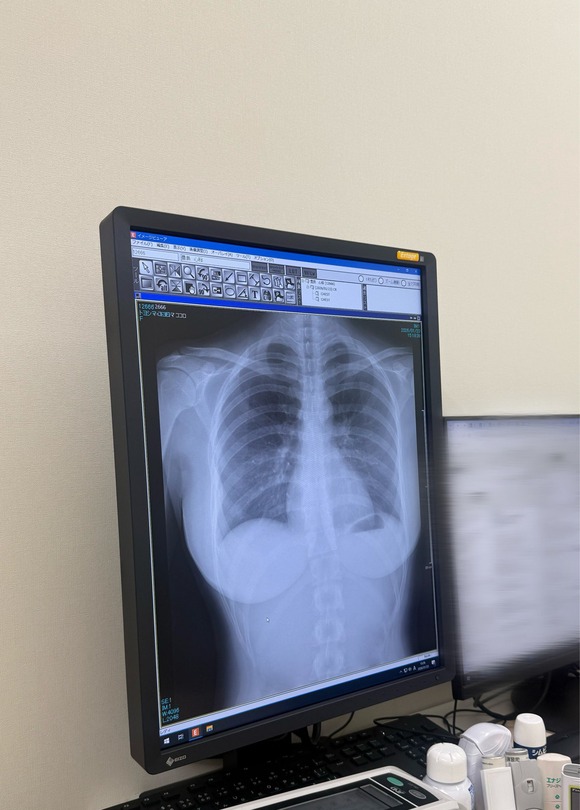

【画像】まんさん、健康診断のレントゲン検査で肺が綺麗なことアピールした結果

【画像】まんさん、健康診断のレントゲン検査で肺が綺麗なことアピールした結果

1: 名無し 2026/01/24(土) 13:28:47.24 ID:LZ1Q1ifJ0

2: 名無し 2026/01/24(土) 13:29:33.31 ID:RD3nA7Zm0

豊胸で草

3: 名無し 2026/01/24(土) 13:30:18.90 ID:s/dV5MVx0

硬そう

4: 名無し 2026/01/24(土) 13:30:27.35 ID:kRu8LWdG0

何か不自然に白いですね…